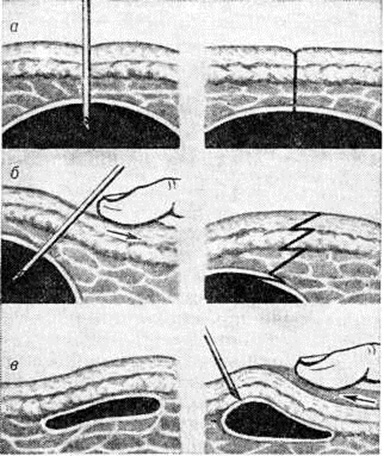

Лечение. В период применения исключительно консервативной терапии костно-суставного туберкулёза борьба с Натечник осуществлялась с помощью паллиативных средств. часть П. Краснобаев (1947) и другие считали, что ведущая роль в лечении Натечник принадлежит пункциям, которые выполняли по определённой методике (рисунок 4) с последующим промыванием полости различными антисептическими средствами. Эта лечебный тактика оказалась мало состоятельной даже в последующем, когда открылись широкие возможности применения специфических противотуберкулёзных препаратов. Расчёт на ликвидацию Натечник без удаления основного очага в кости не оправдался, как и расчёт на его спонтанное излечение. Кардинальное решение проблемы лечения Натечник стало возможным только с развитием радикальной хирургии костно-суставного туберкулёза.

Большинство современных авторов рекомендует применять при Натечник оперативное лечение с ликвидацией туберкулёзного очага в кости — абсцессэктомию и абсцессотомию, которые проводят на фоне антибактериальной и общеукрепляющей терапии. Полное удаление Натечник вместе с капсулой (абсцессэктомия) выполнимо не при всех его локализациях. Операция, как правило, не представляет трудностей на конечностях, но при спондилите, в частности поясничном, вследствие обширности вмешательства нельзя исключить опасности повреждения соседних органов. При некоторых же локализациях Натечник эта операция технически просто неосуществима. Абсцессотомия (удаление содержимого Натечник и его пиогенной оболочки) — более щадящее вмешательство, она обеспечивает не худшие результаты и является менее опасной. В 1953 год П. Г. Корнев впервые применил абсцессотомию по типу предложенной им ранее (1948) укорачивающей фистулотомии с одновременным кюретажем туберкулёзных очагов в телах позвонков. Оперативные вмешательства такого рода оказались более эффективными, чем пункции Натечник